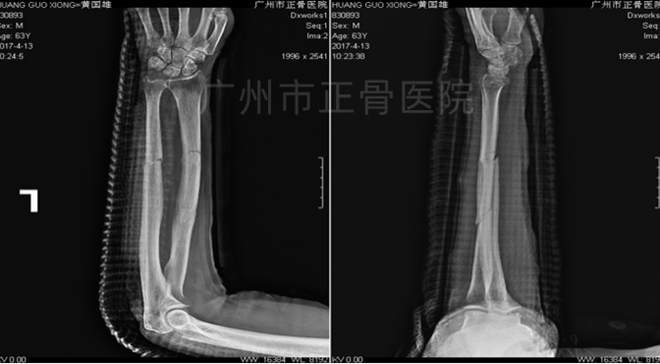

▲6周后,骨痂增多

▲2个月后,骨折线模糊,拆除夹板

▲1年后,骨性愈合